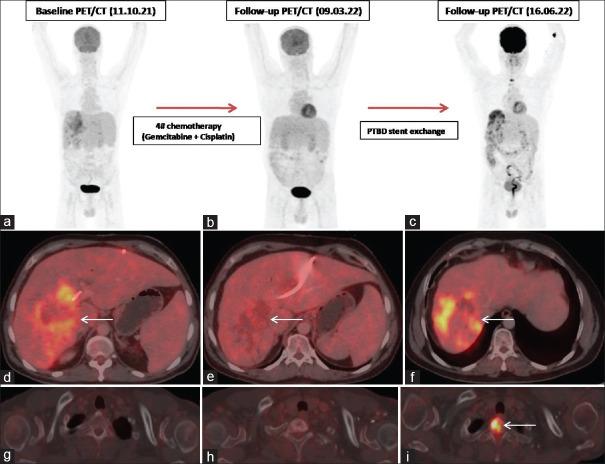

Role of FDG PET/CT in evaluation of biliary tract diseases remains relatively unexplored. PET/CT with FDG helps in evaluation of both infective / inflammatory as well as neoplastic diseases as increased glucose utilization is observed in both the conditions. In this article, we describe the spectrum of FDG PET/CT findings in various diseases affecting the biliary tract. Role of FDG PET/CT in neoplastic diseases involving the biliary duct has been described at the time of staging and response evaluation; in characterization of the intrahepatic mass (abscess v/s cholangiocarcinoma). In addition, we have discussed about the false positive FDG uptake along the biliary duct stent, which interfere with scan interpretation. Few of the benign conditions described are Langerhans cell histiocytosis and IgG4 related disease involving the biliary duct and adenomyomatosis and Xanthogranulomatous cholecystitis involving the gall bladder.

氟代脱氧葡萄糖正电子发射断层显像/计算机断层扫描(FDG PET/CT)在胆道疾病评估中的作用仍相对未被充分探索。含氟代脱氧葡萄糖的PET/CT有助于评估感染性/炎症性疾病以及肿瘤性疾病,因为在这两种情况下均观察到葡萄糖利用率增加。在本文中,我们描述了FDG PET/CT在影响胆道的各种疾病中的表现谱。FDG PET/CT在胆管肿瘤性疾病分期和疗效评估以及肝内肿块(脓肿与胆管癌)鉴别诊断中的作用已被阐述。此外,我们还讨论了沿胆管支架出现的FDG摄取假阳性情况,这会干扰扫描结果的解读。所描述的一些良性疾病包括累及胆管的朗格汉斯细胞组织细胞增多症和IgG4相关疾病,以及累及胆囊的腺肌增生症和黄色肉芽肿性胆囊炎。